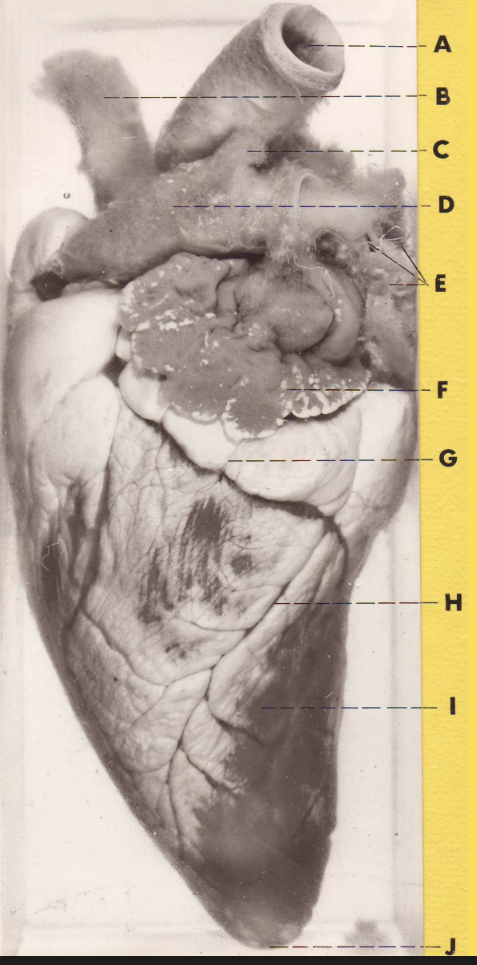

A

(sheep heart)

aorta

B

brachiocephalic trunk

C

ligamentum arteriosum

D

pulmonary trunk

E

pulmonary vv

F

L auricle

G

coronary groove (fatty)

H

intermediate (caudal) groove w/ vessels

I

L ventricular wall

J

apex